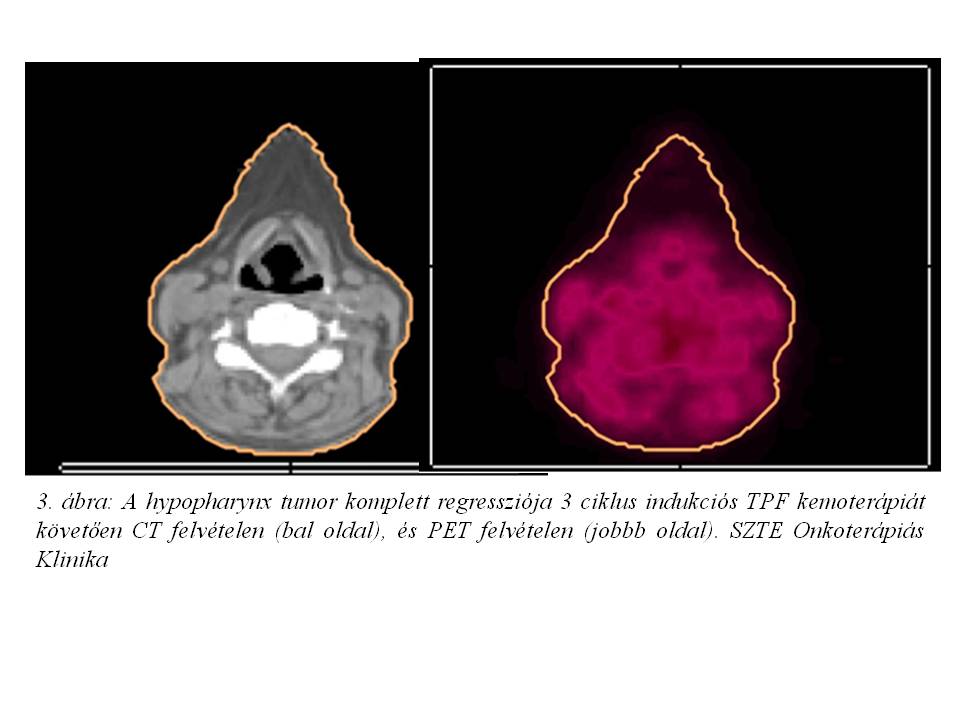

Esetismertetés: Jelenleg 52 éves, 30 éve dohányzó (napi 10 szál cigaretta), alkoholt nem fogyasztó, 20 évvel ezelőtt gyomorfekély miatt műtéten átesett, jelenleg hypothyreosissal kezelt nőbeteg esetét ismertetjük. A beteg 2014 júniusában jelentkezett fül-orr-gégészeten két éve tartó gombócérzés, időnként tapasztalt nyelési nehezítettség és fájdalom, a nyak bal oldalán 1 éve észlelt fájdalmatlan, kemény csomó, 2 hónap alatti 10 kg testsúlyvesztés, és 1 hónapja tartó, antibiotikus kezelésre nem szűnő, a bal fül felé sugárzó torokfájdalom miatt. Fizikális vizsgálat során a fejbiccentő izom elülső széle mentén a parajugularis régióban 2,5 cm átmérőjű, mobilis, ép bőrrel fedett nyirokcsomót észleltek. Rhino-pharyngo-laryngo-fiberoscopia során a bal oldali sinus piriformisban U-alakú, egyenetlen szövetszaporulat és nyálpangás igazolódott. Nyaki és mellkasi CT vizsgálat a hypopharynx régióban, a baloldali sinus piriformist kitöltő, a kontrasztanyagot homogénen és intenzíven halmozó, 20 x 14 x 20 mm nagyságú, a középvonalat meg nem haladó térszűkítő elváltozást, ebben a magasságban baloldalon a vena jugularis internát komprimáló, 20 mm átmérőjű, nekrotikus bennékű metasztázist, valamint a C.II csigolya szintjében dorsalisan egy 2 cm-es, patológiás szerkezetű nyirokcsomót írt le (1. ábra, 2. ábra). A tüdőkben metasztázisra utaló eltérés nem volt (T3 N2 cM0 stádium). Laryngomicroscopia során a bal oldali pharyngo-és aryepiglotticus redőn, illetve a sinus piriformis medialis falán elhelyezkedő teriméből szövettani mintavétel történt, mely közepesen differenciált laphámcarcinomát igazolt. Indukciós TPF kemoterápiát (docetaxel-cisplatin-5-fluorouracil) indítottunk, melynek 1. ciklusát követően a tapintható nyirokcsomó metasztázis eltűnt, a beteg nyelési fájdalmai megszűntek. A kemoterápia harmadik ciklusát követően fül-orr-gégészeti vizsgálat során makroszkópos tumor nem volt látható, az elvégzett PET/CT vizsgálat során FDG-avid malignitás nem igazolódott (3. ábra, 4. ábra). Jelenleg a beteg definitív sugárkezelését végezzük.